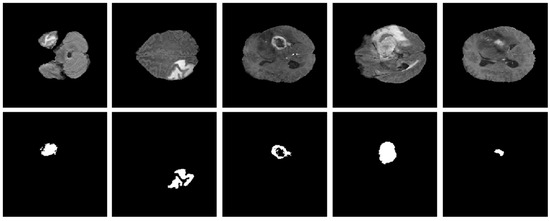

| Results | ET | TC | WT | Heterogeneous | ||||

|---|---|---|---|---|---|---|---|---|

| Figure 11a | Figure 11b | Figure 12a | Figure 12b | Figure 13a | Figure 13b | Figure 14a | Figure 14b | |

| FD | 1.1956 | 1.1312 | 1.2887 | 1.2562 | 1.5601 | 1.4406 | 1.0776 | 1.3711 |

| R2 | 0.957 | 0.934 | 0.983 | 0.96 | 0.982 | 0.98 | 0.983 | 0.954 |

| C | 0.9783 | 0.9665 | 0.9915 | 0.9799 | 0.9909 | 0.9901 | 0.9913 | 0.9768 |